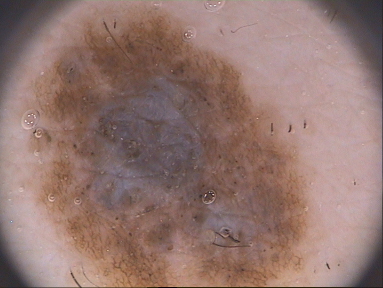

Dermofit Refer to caption Refer to caption Refer to caption Refer to caption

EDRA/Clinic Refer to caption Refer to caption Refer to caption Refer to caption

EDRA/Dermato Refer to caption Refer to caption Refer to caption Refer to caption

ISIC Archive Refer to caption Refer to caption Refer to caption Refer to caption

PH2 Refer to caption Refer to caption Refer to caption

Figure 1: Samples of skin lesion images. Rows: datasets used in this work. Columns: types of lesions. The first two rows are clinical images; the others are dermoscopic images. Note that the EDRA samples are the same lesion captured in each of the techniques. The PH2 dataset does not have Keratosis lesions.